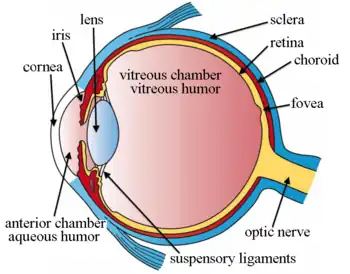

Cross-section of human eye, with choroid labeled at top. | |

Schematic cross section of the human eye; choroid is shown in purple.

The interior of the posterior half of the left eyeball Structures of the eye labeled

Structures of the eye labeled This image shows another labeled view of the structures of the eye